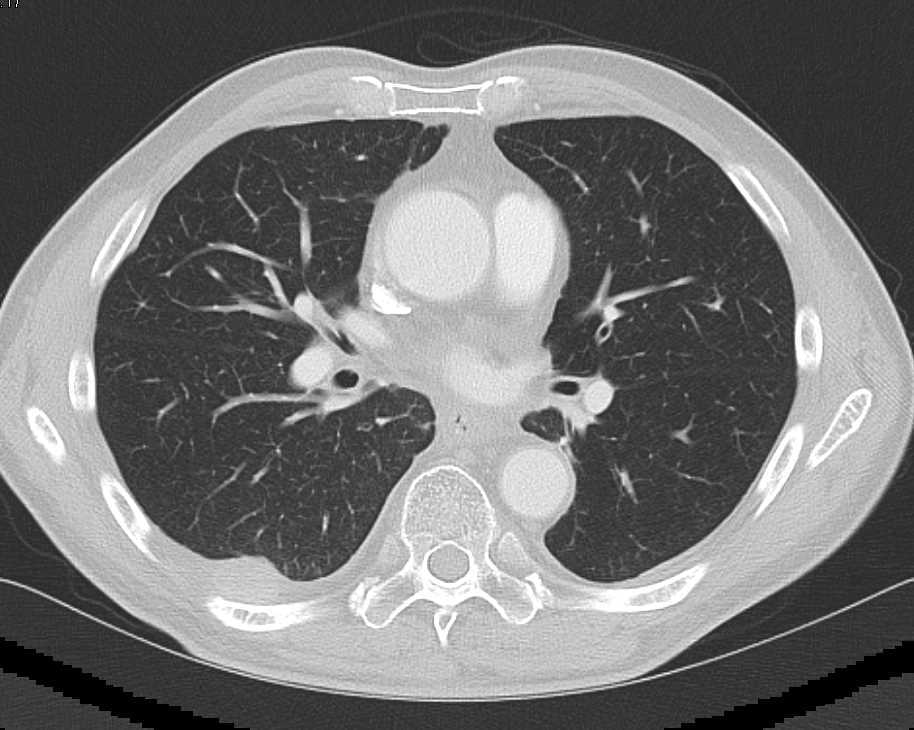

Metastatic Colon Cancer to Liver with Portal Adenopathy and Metastases to Sternum